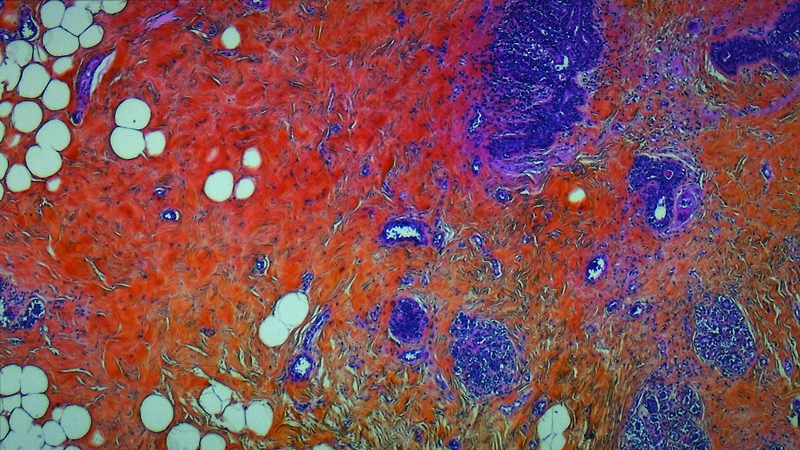

内臓も眼球も無修正で全部見せる!医者の愚痴まで丸聞こえの解剖ドキュメンタリー『人体の構造について』